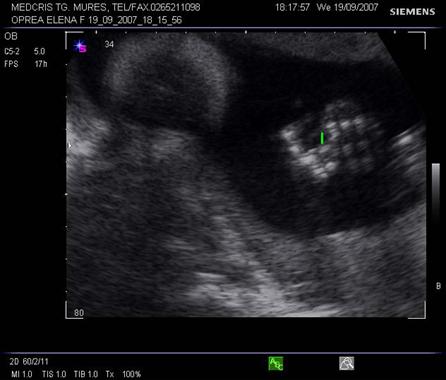

Planul III sau planul frontooccipital, pentru masurarea diametrelor biparietal si frontoocipital. Ecoul de mijloc frontoocipital este intrerupt in zona cavum septum pellucidi, anecogena, situata anterior de ventriculul III. Acesta este situat intre doi nuclei talamici hipoecogeni si apare ca o despicatura mica sau o linie.

Fig. nr. 151 Planul III de sectiune transversala a craniului fetal.